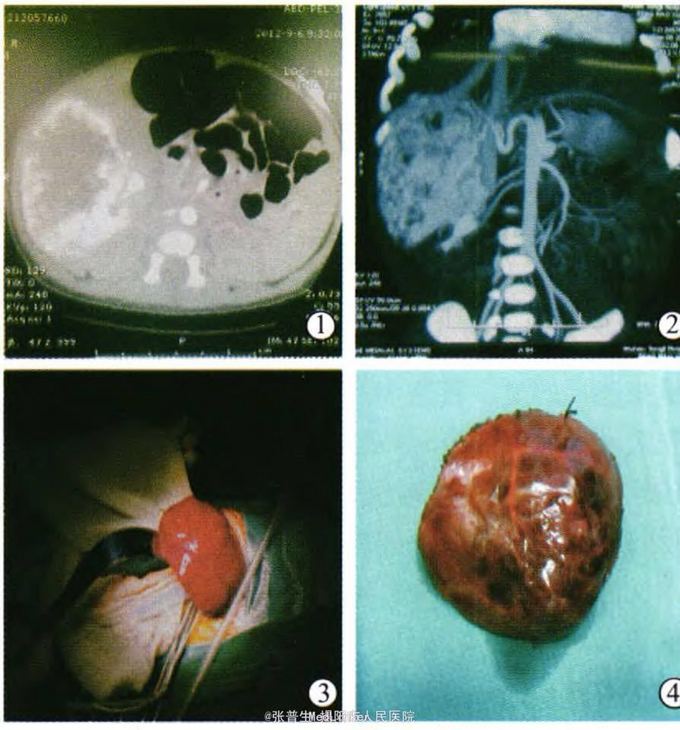

患儿男,3天。因发现肝脏包块入院。孕母产前B超发现肝右叶包块。

查体:腹软,肝肋下3cm,脾未触及。AST57,总胆高,以直胆为主,AFP3+万ng/ml.CT示肝脏包块4*5cm,肝动脉期强化,门静脉期明显强化,延迟期呈低密度灶。考虑肝母细胞瘤。

处理:行肝母细胞瘤切除术,肿块表面见较多扩张血管。完整切除肿瘤。术后病理:肝母细胞瘤(单纯胎儿型)。术后15天复查血常规 生化 B超无明显异常遂出院。